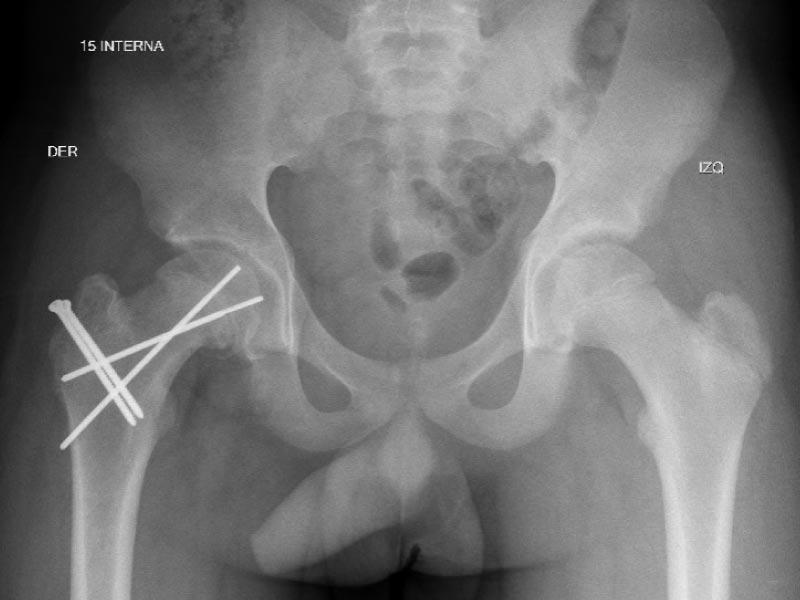

Caso No. 4 - Deslizamiento epifisiario

Preoperación

Posoperación

Deslizamiento Epifisiario Femoral

Diagnóstico: deslizamiento epifisiario femoral proximal crónico derecho

Tratamiento quirúrgico: luxación quirúrgica de la cadera derecha y realineación de la cabeza femoral.